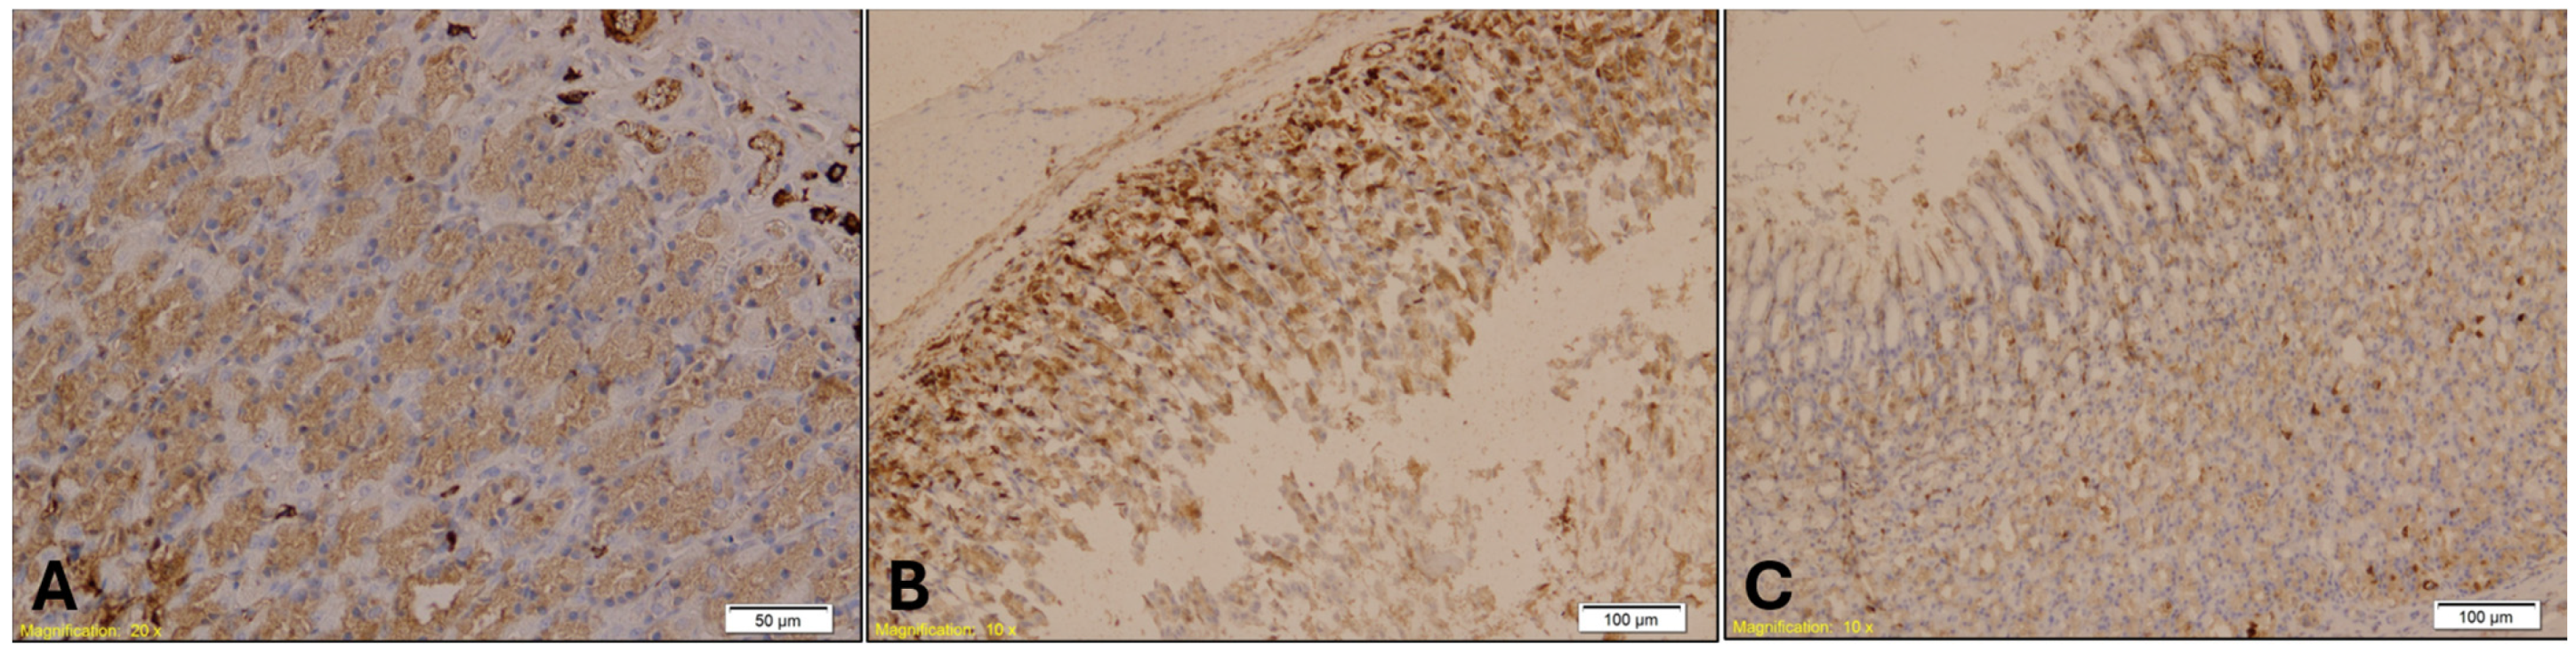

- Cytokeratin 7 (CK7) (rabbit monoclonal, 1:100)—Gastroesophageal Junction: CK7 is an intermediate filament protein expressed in epithelial cells, particularly in glandular and transitional zones. Its expression helps assess epithelial integrity and stress responses in hypothermia-related gastrointestinal injury.

- Cytokeratin 20 (CK20) (mouse monoclonal, 1:150)—Gastroesophageal Junction: CK20 complements CK7 in characterizing epithelial differentiation and stress. Its expression pattern can help distinguish hypothermia-induced epithelial changes from other causes of mucosal injury.

| CK7 | Cytokeratin 7 |

| CK20 | Cytokeratin 20 |